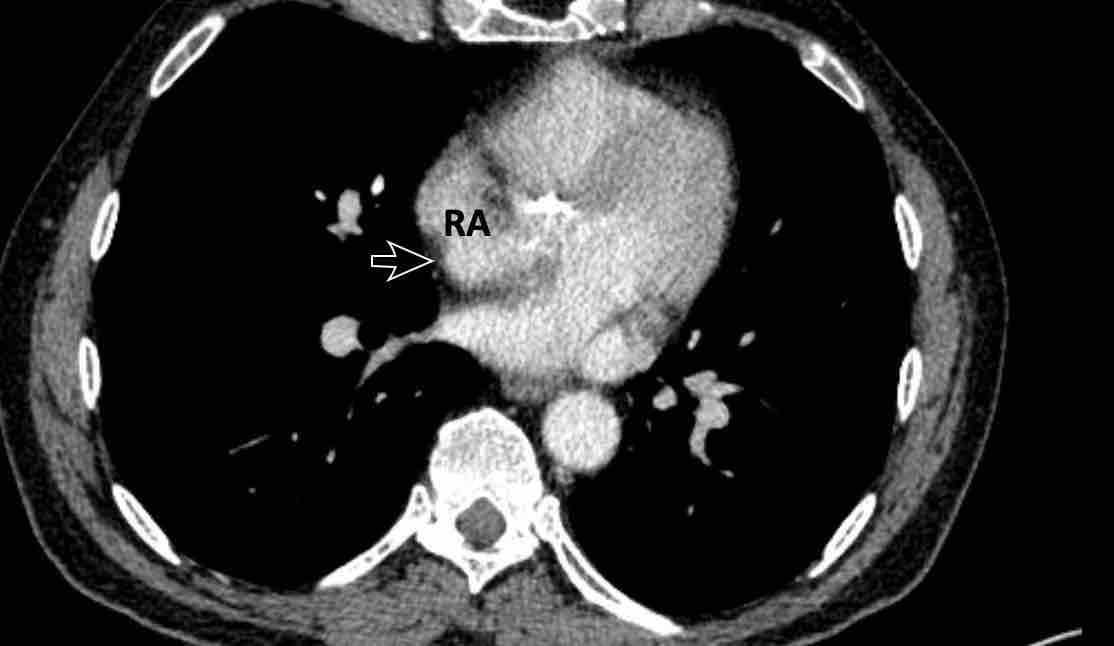

Hình ảnh

Sùi nhiễm khuẩn khổng lồ trên van ba lá ở một người dùng heroin qua đường tĩnh mạch bị viêm nội tâm mạc do S. Aureus.